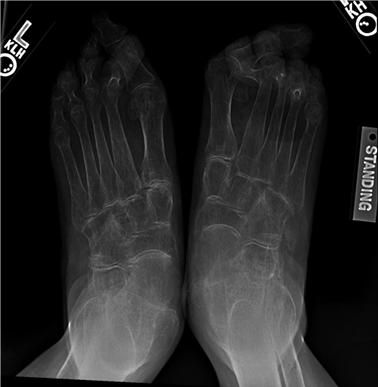

Weight-bearing anteroposterior (AP), lateral, and sesamoid axial radiographs are mandatory. On the AP view, the surgeon measures the Hallux Valgus Angle (HVA, normal < 15°), the Intermetatarsal Angle (IMA, normal < 9°), and the Distal Metatarsal Articular Angle (DMAA). The lateral view is scrutinized for Meary's angle (talo-first metatarsal angle) to identify midfoot collapse, as well as the presence of dorsal osteophytes indicative of hallux rigidus. The sesamoid axial view is critical for assessing the degree of sesamoid subluxation and the integrity of the crista.

Epidemiologically, hallux valgus alone affects nearly 23% of adults aged 18 to 65 years and over 35% of individuals older than 65 years, with a pronounced predilection for the female demographic. This gender disparity is classically attributed to a combination of intrinsic ligamentous laxity, hormonal influences, and extrinsic factors such as constrictive, narrow-toebox footwear with elevated heels. However, modern orthopedic consensus increasingly acknowledges the polygenic, hereditary nature of first ray deformities. Patients frequently exhibit a positive family history, suggesting an underlying genetic predisposition to metatarsus primus varus, hypermobility of the first tarsometatarsal (TMT) joint, or anomalous articular morphology.

The pathophysiology of first metatarsal disorders is fundamentally rooted in biomechanical failure. In the context of hallux valgus, the initial destabilization often occurs at the first TMT joint or the metatarsophalangeal (MTP) joint, leading to medial deviation of the first metatarsal and lateral subluxation of the proximal phalanx. As the deformity progresses, the intrinsic musculature—specifically the adductor hallucis—gains a mechanical advantage, further exacerbating the valgus drift and pronation of the hallux. Concurrently, the sesamoid apparatus remains tethered to the transverse metatarsal ligament, resulting in relative lateral subluxation of the sesamoids as the metatarsal head drifts medially.